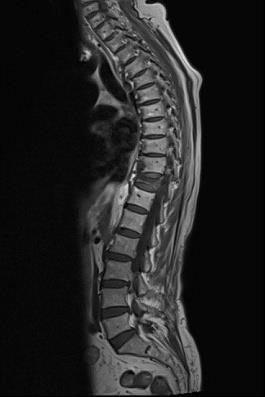

In the modern physical therapy world, accurate understanding of body posture is no longer limited to traditional judgments of "good" or "bad". Instead, posture is considered as a starting point for designing a personalized treatment pathway. Investigating the type of body posture can play a central role in diagnosing the pattern of movement disorders and determining treatment strategies.

In this type of condition, which is characterized by increased spinal arches, postural muscles tend to become inactive. This puts an additional burden on other structures such as joints, ligaments, and accessory muscles. In this situation, the physiotherapist should focus on activating the core muscles and improving muscle control.

In this state, which is associated with excessive stretching of the trunk and shoulders back, the postural muscles tend to be overactive. This condition leads to muscle stiffness, chronic pain and reduced flexibility. The treatment solution in this case is to reduce the pressure and allow the muscles to work in different ranges of motion.

In the past, "good" posture was defined as being close to the anatomical ideal. But today it is clear that what is important is the suitability of the position with functional needs, muscle strength and individual characteristics. In other words, physical condition is not only an appearance criterion, but also a functional criterion for choosing the path of rehabilitation.